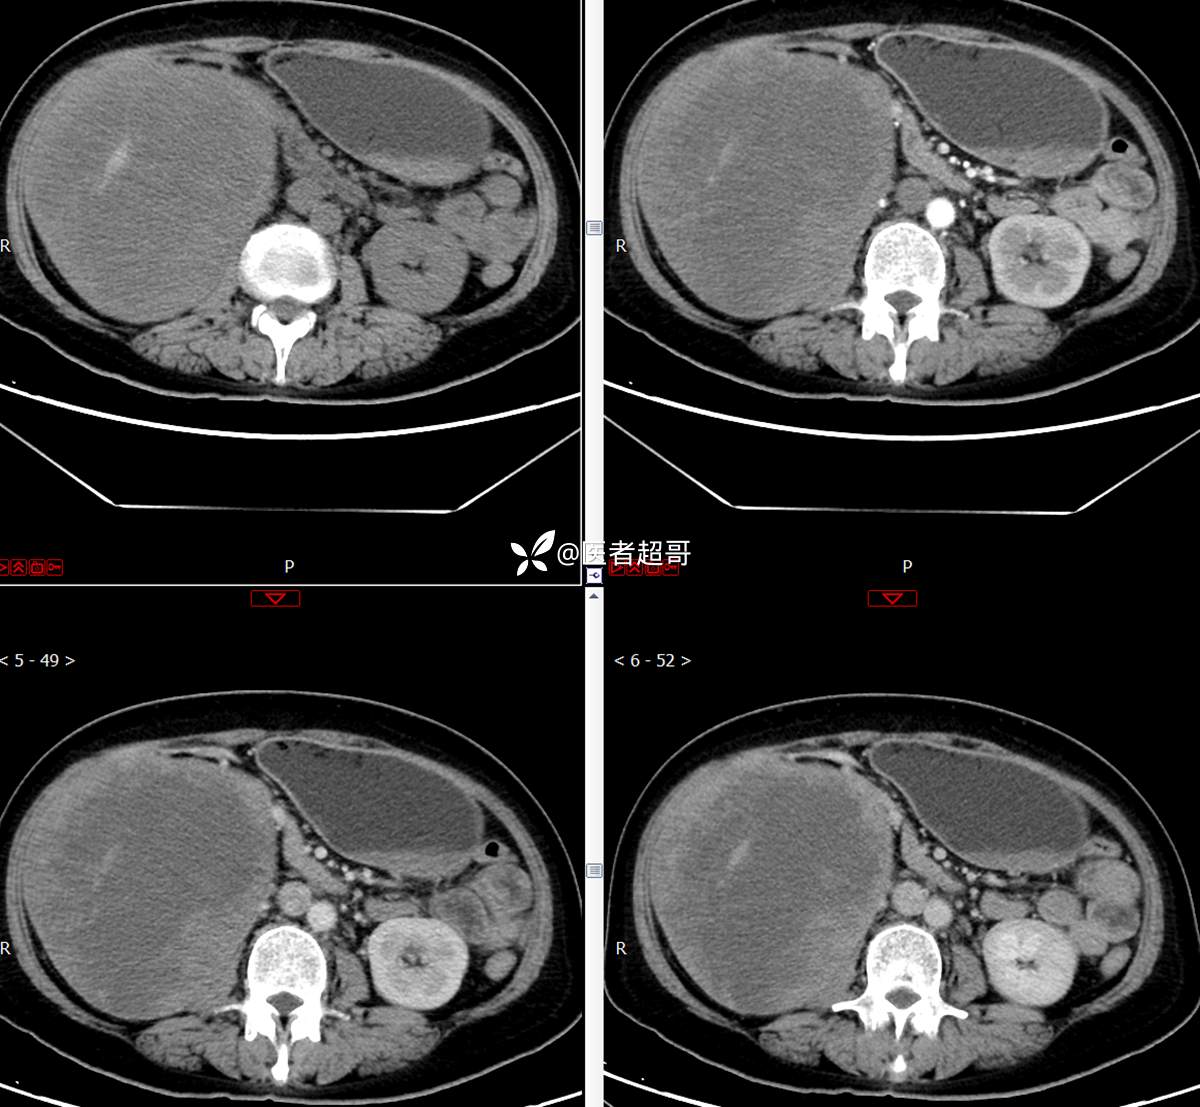

现病史:患者1周余前发现右上腹有一半球形巨大肿物,约18cm*15cm大小,既往贫血病史3年余,诉乏力,易疲劳,偶有头晕,活动后心悸,无腹痛、腹胀,无恶心、呕吐,无尿频、尿急、尿痛,无排尿困难,患者为求进一步治疗,来我院消化内科就诊,门诊行肝.胆.胰.脾.肾彩超示:右肾上部囊实性占位,范围约18.0cm×11.7cm×16.4cm,边界清,形态规则,建议进一步检查,腹膜后实性结节。我科遂以“肾肿物”收治入院,患者自发病以来,神志清、精神可,睡眠、饮食可,二便正常,体重、体力略有下降。